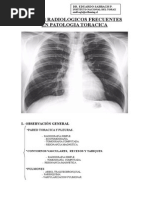

¿Cuál de las 4 radiografías es la normal?

1) Se observa una cavitación, lo más probable es que el paciente sea tuberculoso. Si

comparamos la base pulmonar derecha con la izquierda, hay opacidad basal derecha con

consolidación. En el pulmón izq no hay cambios radiológicos

2) El cayado aórtico prominente es fisiológico en pacientes añosos. Tiene un

compromiso del intersticio pulmonar. Tiene covid. En la aorta hay ensachamiento.

3) Masa paracardiaca derecha, ensachamiento del mediastino. Masa tumoral.

4) Rx anteroposterior, esta es la normal. El timo es lo que se proyecta. Vela de barco.